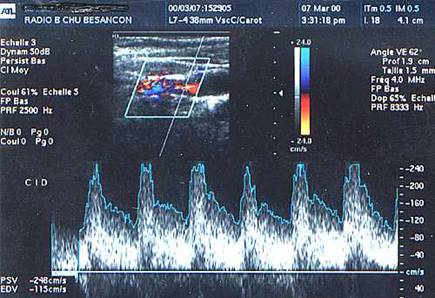

Doppler pulsatil, carotida comuna

Doppler pulsatil (pic sistolic 250

cm/s).